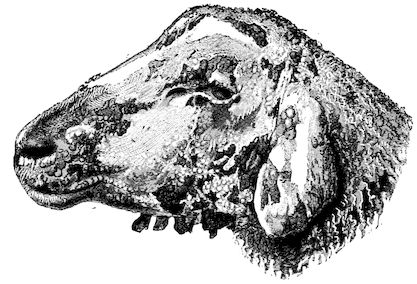

| Scabies—Scab—Mange | 611 | |||

| Scabies in sheep | 611 | |||

| Sarcoptic scabies | 612 | |||

| Psoroptic mange—Sheep scab | 614 | |||

| Chorioptic mange—Symbiotic mange—Foot scab | 636 | |||